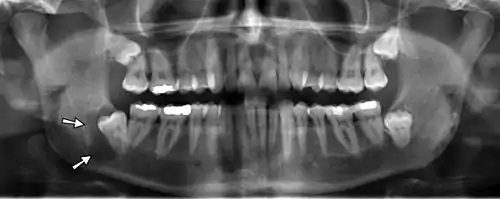

On an x-ray, cysts appear as radiolucent (dark) areas with radiopaque (white) borders. [7]However, cysts in maxillary sinus, also known as antrum, can appear radiopaque as the surrounding air absorbs fewer photons than the cystic fluid content.